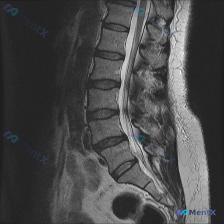

整理到一份病例影像资料,有点意思,放出来和大家讨论下读片思路。 首先说明:这是一张腰椎矢状位T2WI MRI,用户最初问的是「能不能看到脊柱侧弯」。 先把影像里能看到的点列一下: - 从L1/L2到L5/S1,椎间盘T2信号都低了,髓核高信号基本没了,典型「黑盘征」 - L4/L5、L5/S1椎间盘...

整理了一份影像分析讨论素材,大家先别着急看预设答案,聊聊第一眼思路: 用户一开始问的是「这张图片明显可见的病症是脊柱侧弯吗」,但提供的只有腰椎MRI T2加权矢状面这一个序列。 先把影像里能看到的客观表现列出来: 1. 椎间盘:全腰椎T2信号普遍减低(黑盘征),L4/5、L5/S1椎间隙变窄,且有明...

整理了一份腰椎影像资料,先跟大家同步一下情况: 用户提到了“脊柱侧弯”,但目前手里只有腰椎MRI-T2序列的矢状位影像,没有冠状位的片子。 先说说这份矢状位上能看到的点: 1. 多节段椎间盘T2信号减低,L2/3、L3/4、L4/5、L5/S1都有“黑盘”征 2. L4/5明显向后突,压到硬膜囊前缘...